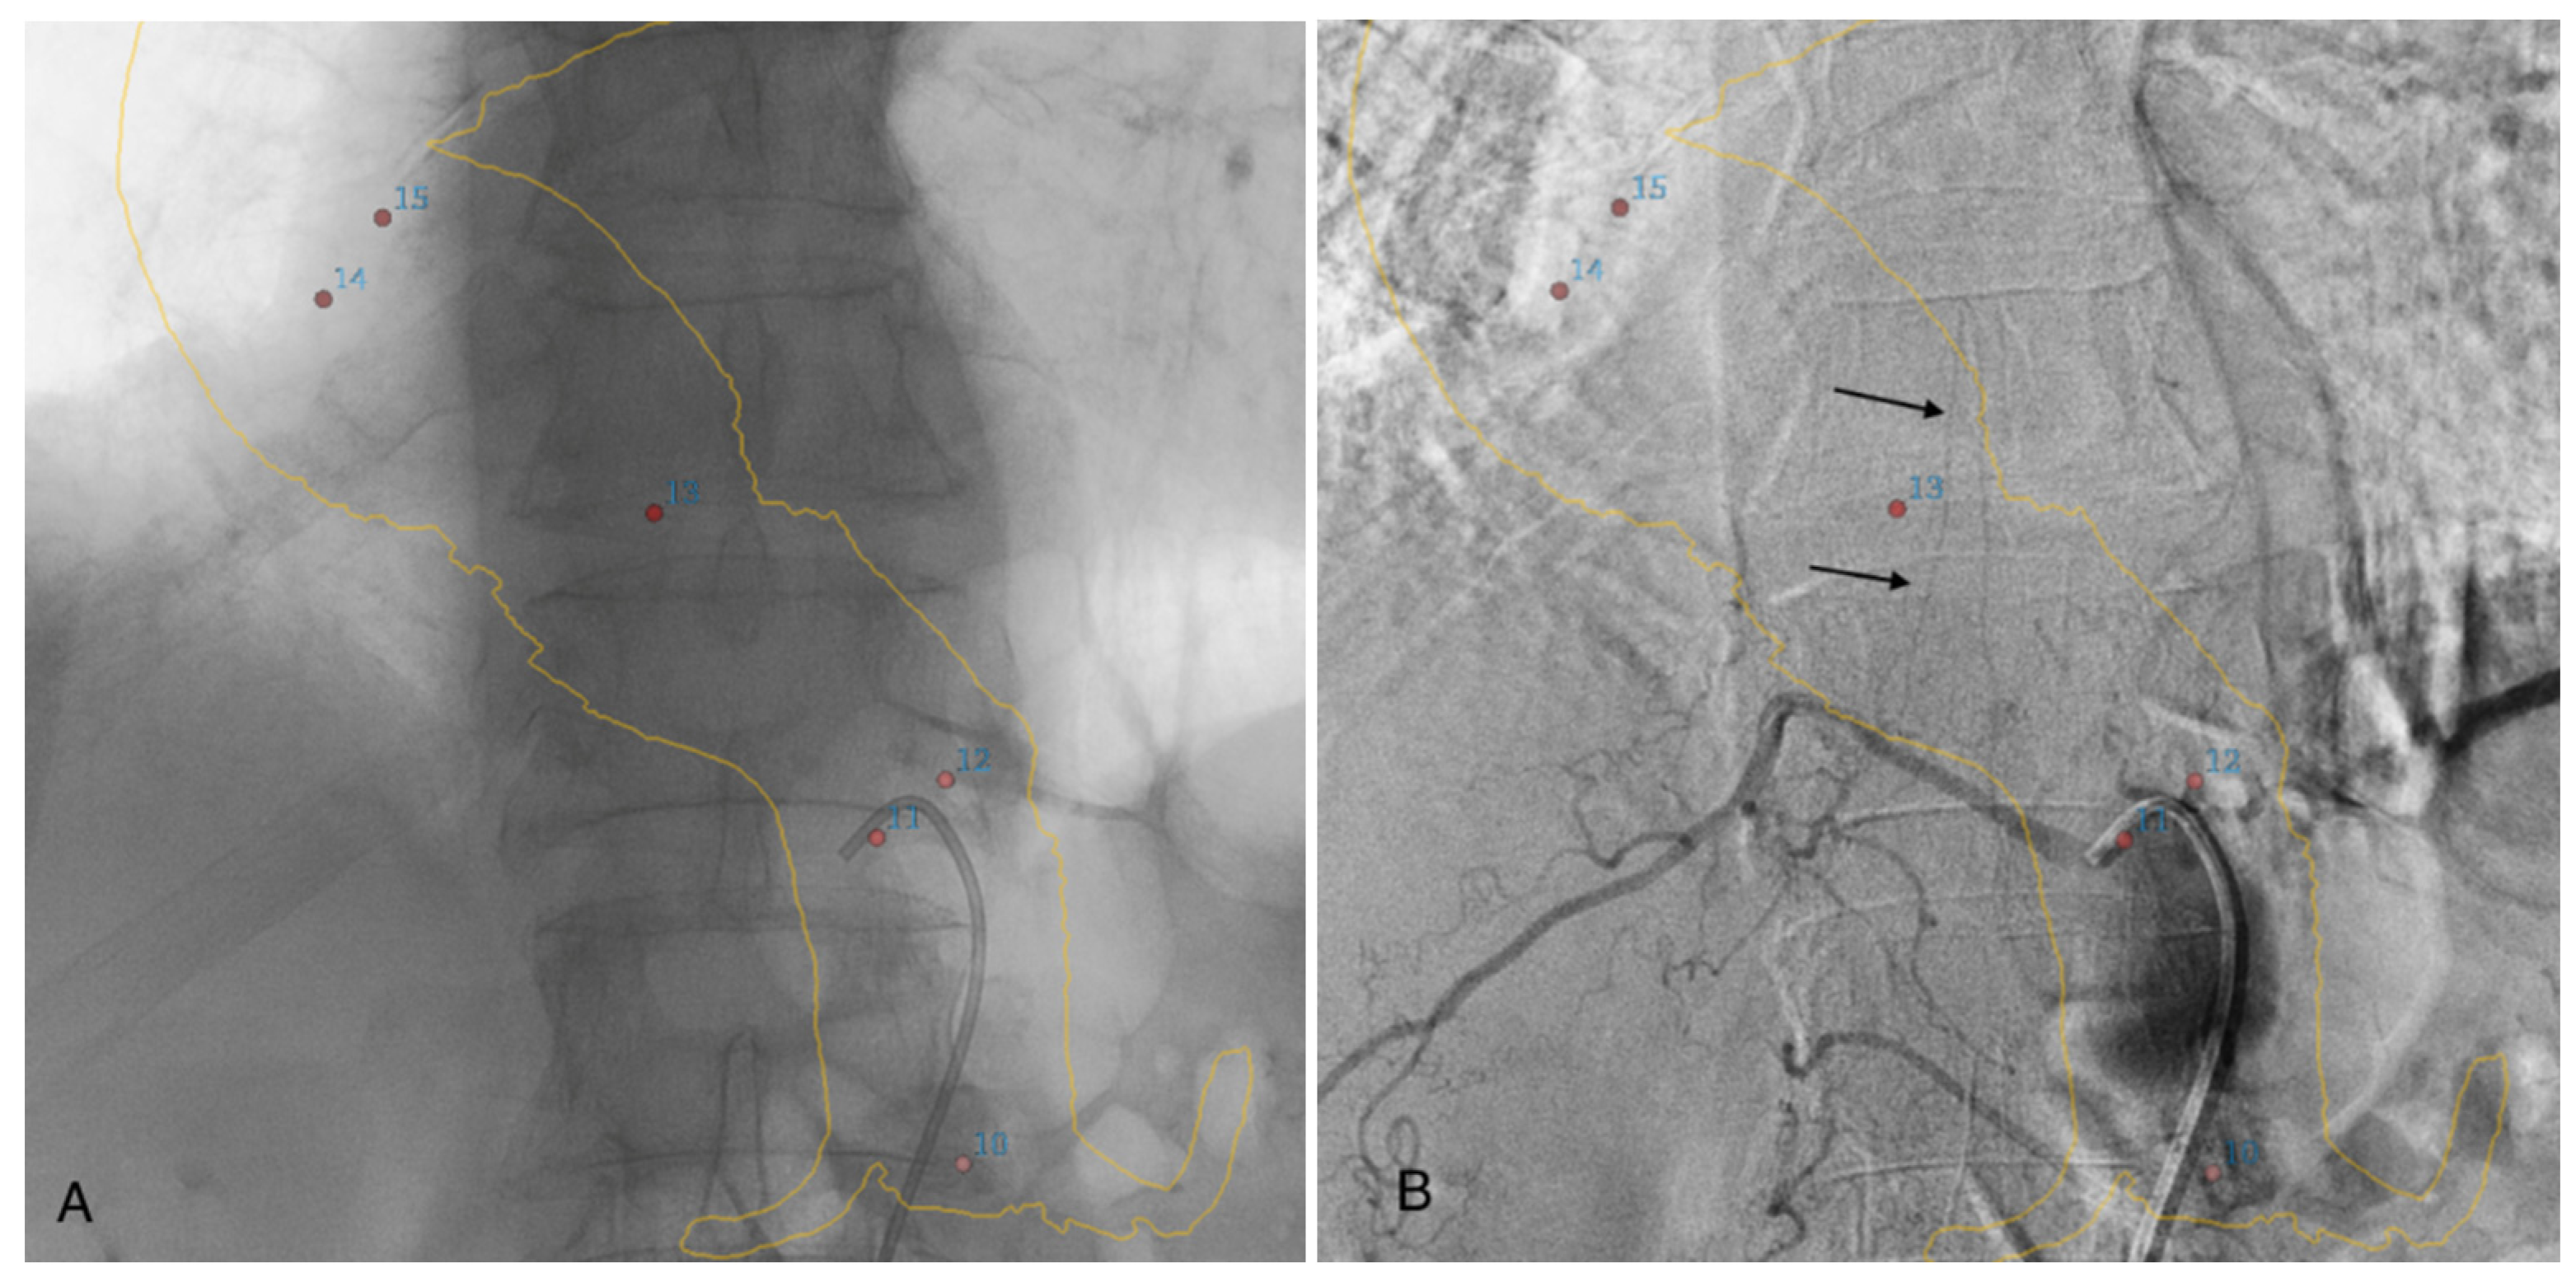

2.2. Diagnostic Angiography Procedure